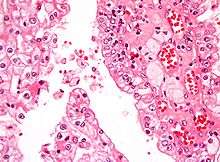

Micrograph showing the most common type of kidney cancer (clear cell renal cell carcinoma). H&E stain. | |

The two most common types of kidney cancer are renal cell carcinoma (RCC) and transitional cell carcinoma (TCC, also known as urothelial cell carcinoma) of the renal pelvis. These names reflect the type of cell from which the cancer developed.

The different types of kidney cancer (such as RCC and UCC) develop in different ways, meaning that the diseases have different long term outcomes, and need to be staged and treated in different ways. RCC is responsible for approximately 80% of primary renal cancers, and UCC accounts the majority of the remainder.[1]